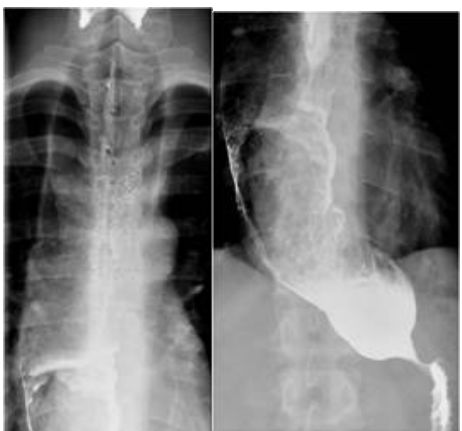

72.23歲男性,主訴吞嚥困難與經常性吸入性肺炎,上消化道鋇劑攝影檢查如下圖,最有可能的診斷為: (A)achalasia (B)gastroesophageal reflux disease(GERD) (C)gastric lymphoma (D)hiatal hernia